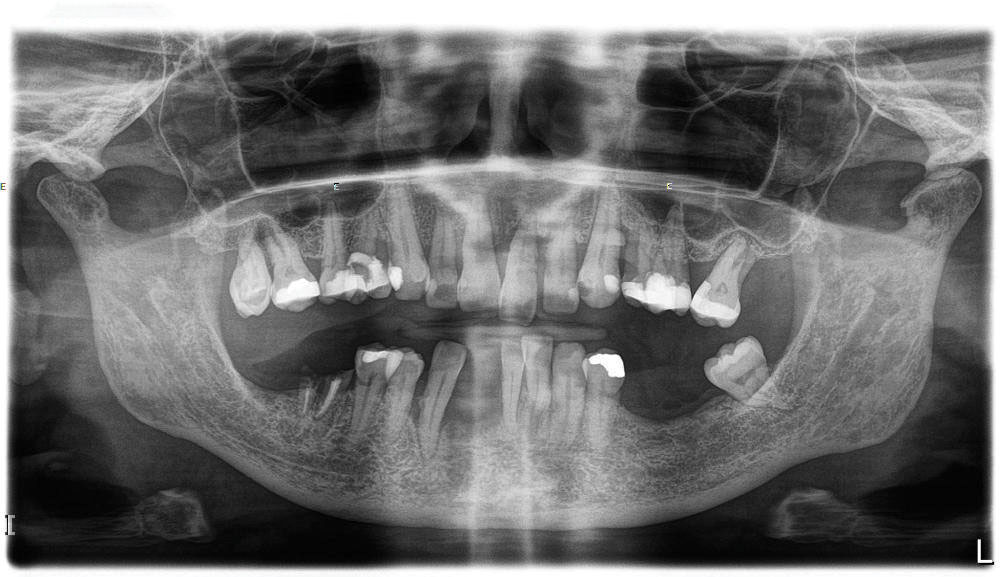

At the initial visit, a panoramic x-ray (Figure 11) and periapical x-rays were taken. The patient was photographed to capture her full face and shoulders, and a digital scan of the maxillary dentition was obtained. This file was electronically sent to the implant company to complete the VSD.

Fig 11. Initial panoramic radiograph.

Figure 11